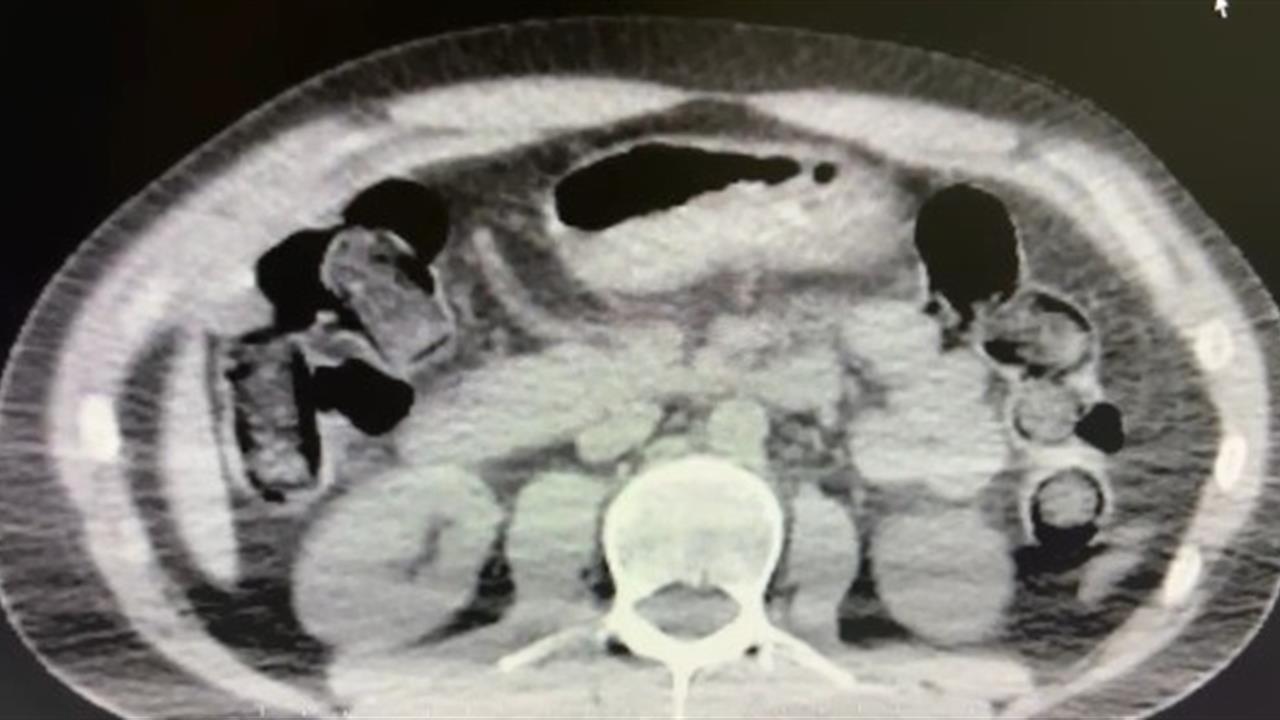

Nevşehir İl Emniyet Müdürlüğü Narkotik Suçlarla Mücadele Şube Müdürlüğü ekipleri, kentte uyuşturucu ve uyarıcı madde ticareti yapan kişilere yönelik kapsamlı bir operasyon başlattı. Cumhuriyet Başsavcılığı'nın koordinesinde yürütülen çalışmalarda, şüpheliler S.B. ve O.R.’nin 'yutma yöntemi' kullanarak uyuşturucu madde sevk edeceği bilgisi alındı. Bu bilgi üzerine harekete geçen ekipler, belirlenen adreslerde ve araçlarda detaylı arama gerçekleştirdi. Yapılan aramada, 101 kapsül halinde toplam 722 gram uyuşturucu madde, bir adet hassas terazi ve bu yöntemle uyuşturucu sevkiyatında kullanılan farklı materyaller ele geçirildi. Ayrıca, uyuşturucu ticaretinden elde edildiği değerlendirilen 20 bin 210 TL, bin 320 euro ve 10 ABD doları da bulundu. Emniyetteki işlemlerinin ardından adliyeye sevk edilen iki şüpheli, çıkarıldıkları mahkemece tutuklanarak cezaevine gönderildi.

Nevşehir'de düzenlenen operasyonda midelerinde uyuşturucu taşıyan iki kişi tutuklandı. Polis, sokak satıcılarına yönelik yürüttüğü çalışmada, şüphelilerin yutma yöntemiyle uyuşturucu sevk ettiğini belirledi.